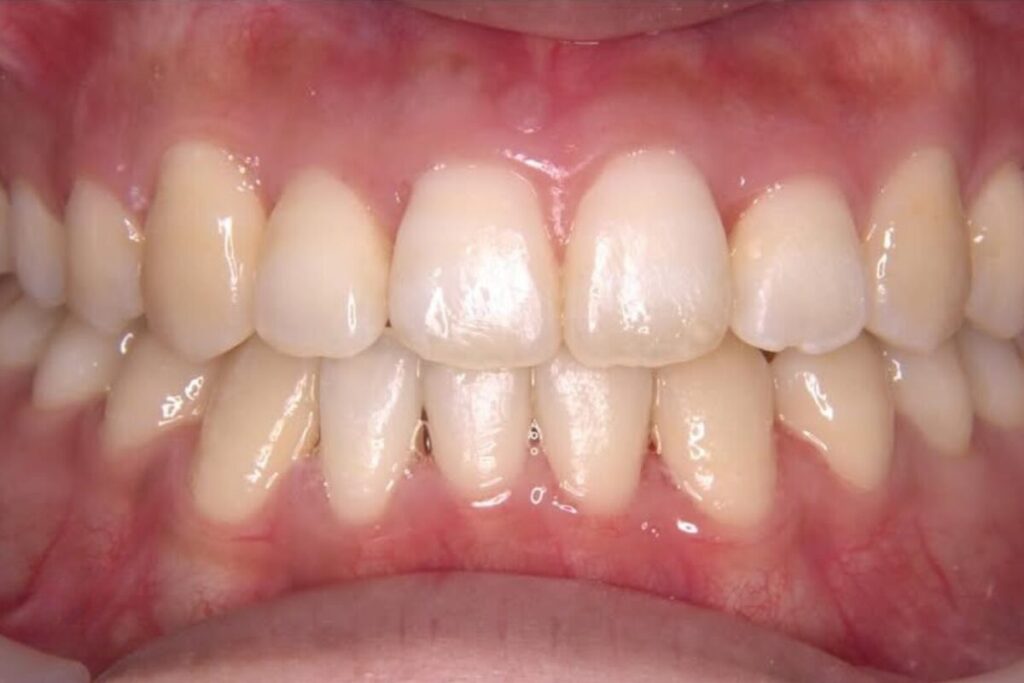

| 患者 | 28歳男性 |

|---|---|

| 主訴 | 歯ならびのガタガタ |

| 診断名 | UR7/LR7クロスバイトと上下叢生を伴うAngleⅠ級sk.1不正咬合 |

| 治療内容 | マウスピース型矯正装置(インビザライン)、部分的に上顎前歯部にワイヤー併用 |

| 抜歯の有無 | 非抜歯 |

| 治療期間 | 2年 |

| 費用(税込) | 594,000円 |

| リスクと副作用 | 痛み等、歯根吸収/歯肉退縮、後戻り、むし歯・歯肉炎の可能性。 |

【医師コメント】

上下のガタつきで来院された患者さんです。

精密検査の結果、UR7/LR7のクロスバイト(交叉咬合)と上下の叢生を伴う AngleⅠ級(sk.1)不正咬合 と診断しました。奥歯の前後関係はⅠ級で大きなズレは強くない一方、奥歯の噛み合わせのズレとスペース不足が原因でした。

治療はインビザラインを主体に非抜歯で計画し、歯列全体のバランスとかみ合わせの安定を意識しながら段階的に改善を進めました。

終盤、UL2のローテーションがわずかに残ったため、仕上げの精度を高める目的で上顎前歯部に部分的にワイヤーを併用しています。

治療は計画に沿って進行し、2年で歯列の配列とかみ合わせの改善を図ることができました。